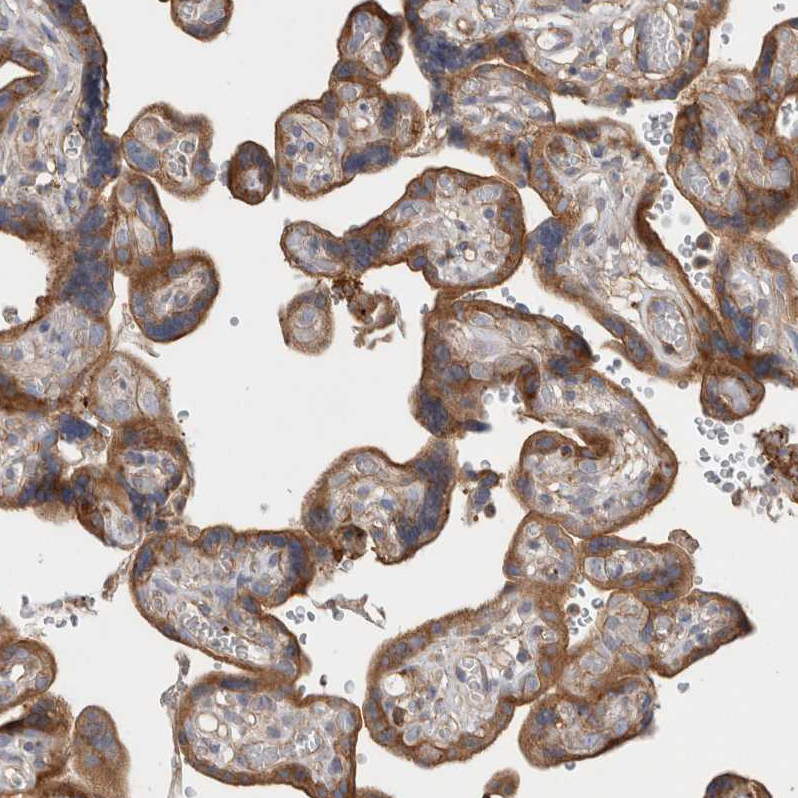

Immunohistochemical staining of human placenta shows moderate cytoplasmic positivity in trophoblastic cells.